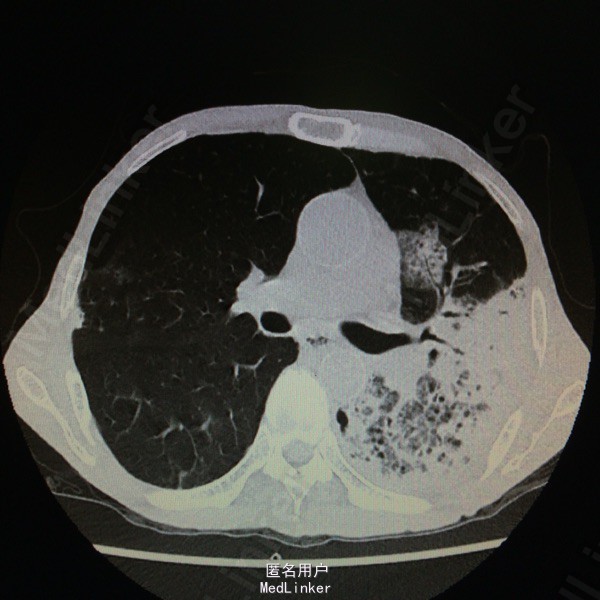

查体:T37.7度,P130次/分,BP 77/59次/分,神情,恶病质,双肺呼吸音粗,未及干湿罗音。 辅助检查:胸部CT示:双肺感染、左肺实变部分坏死。支气管镜示:左上叶气管黏膜感染:真菌?结核?黏膜病理报:符合真菌感染,形态学考虑为曲菌。多次痰培养示:曲霉菌感染。白细胞 12.9*10E9/L,CRP 140ng/ml,ESR 140mm/h,PCT 0.676ng/ml。

随访:患者现予“伏立康唑、两性B”治疗,体温正常,咳嗽咳痰明显好转。复查胸部CT示:左肺上叶病变较前进展,下叶病变较前吸收,左肺实变部分坏死空洞范围较前扩大。 讨论:据痰培养及病理,可明确诊断“肺曲霉菌感染”;予两性霉素B治疗后体温可降至正常,支持该患者发热为曲霉菌感染所致。痰培养及病理结果均支持曲霉菌感染的病例还是少见的。就患者体温变化而言,示治疗有效;其胸部CT示左肺坏死空洞较前扩大,其左肺大部分为坏死组织,空洞会随着这些组织的排出而变大。